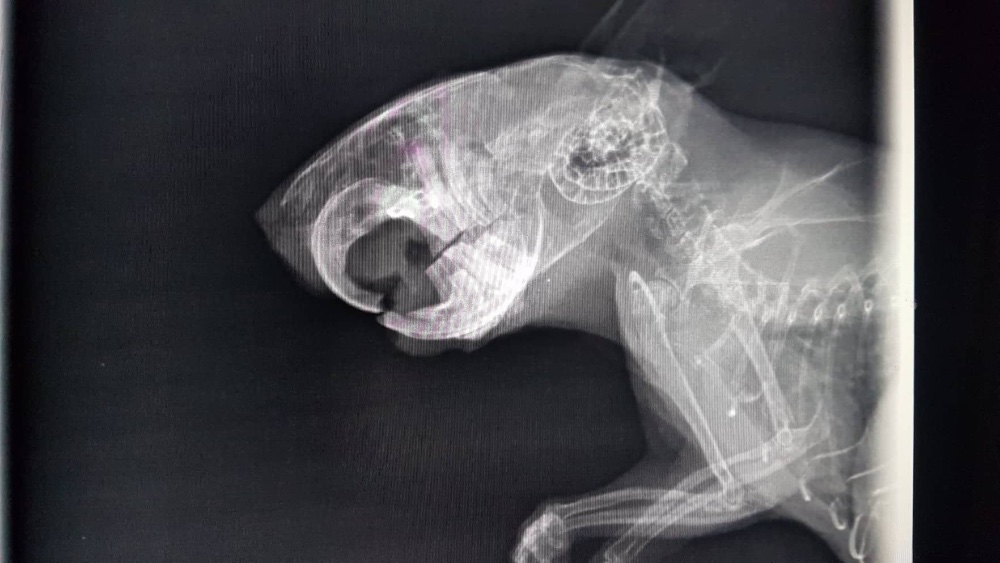

Also ab zum Tierarzt. Sie hat keine Veränderungen feststellen können - auch im Röntgenbild nicht. Er hat aber gefressen, nur eben langsam und eher die weichen Sachen. Nach ein paar Tagen wurden dann auch die unteren Schneidezähne schwarz

Und dann... tja, dann sind irgendwie alle Zähne nacheinander abgebrochen und sind in wunderschönem, gelblichen, gesunden Farbton wieder gekommen. Okay... ich verstehe es nicht, bin aber erstmal zufrieden. Trotzdem isst der blinde Zauberer nur mäßig festes Futter, schlingt aber den Brei. Also wieder mal zum Doc, wieder die Zähne gemacht, ein paar Spitzen geschliffen, aber sonst hat er gute Zähne. Auch das Röntgenbild scheint das zu bestätigen.

So... jetzt unterhalten Merlin und ich uns gestern Abend ein bisschen, und da fällt mir auf, wie unfassbar falsch seine Zähne wachsen... Ich habe das mal versucht aufzuzeichnen, weil ich das so nicht erklären kann. Ich hoffe ihr seht es. Die wachsen irgendwie nicht nach unten, sondern nach INNEN

Und wenn ich mir sein letztes Röntgenbild so ansehe... irgendwie (jetzt wo man es weiß) sieht es schon da irgendwie anders aus, als hier

- merlin_roentgen.jpg (136.79 KiB) 2442 mal betrachtet